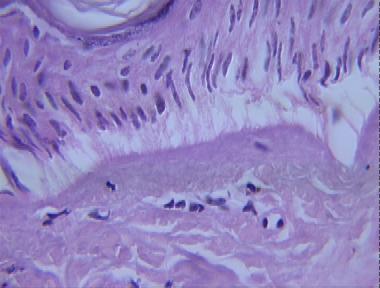

electric burn

Histologic Features